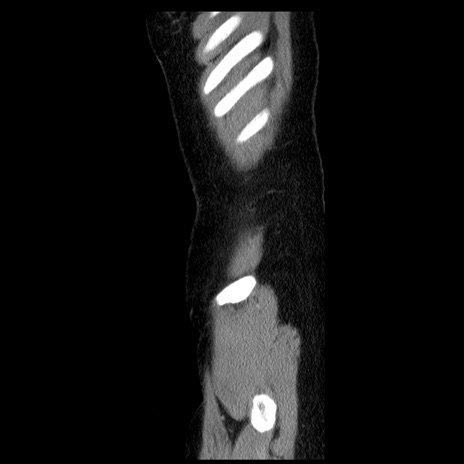

症例6(矢状断像)